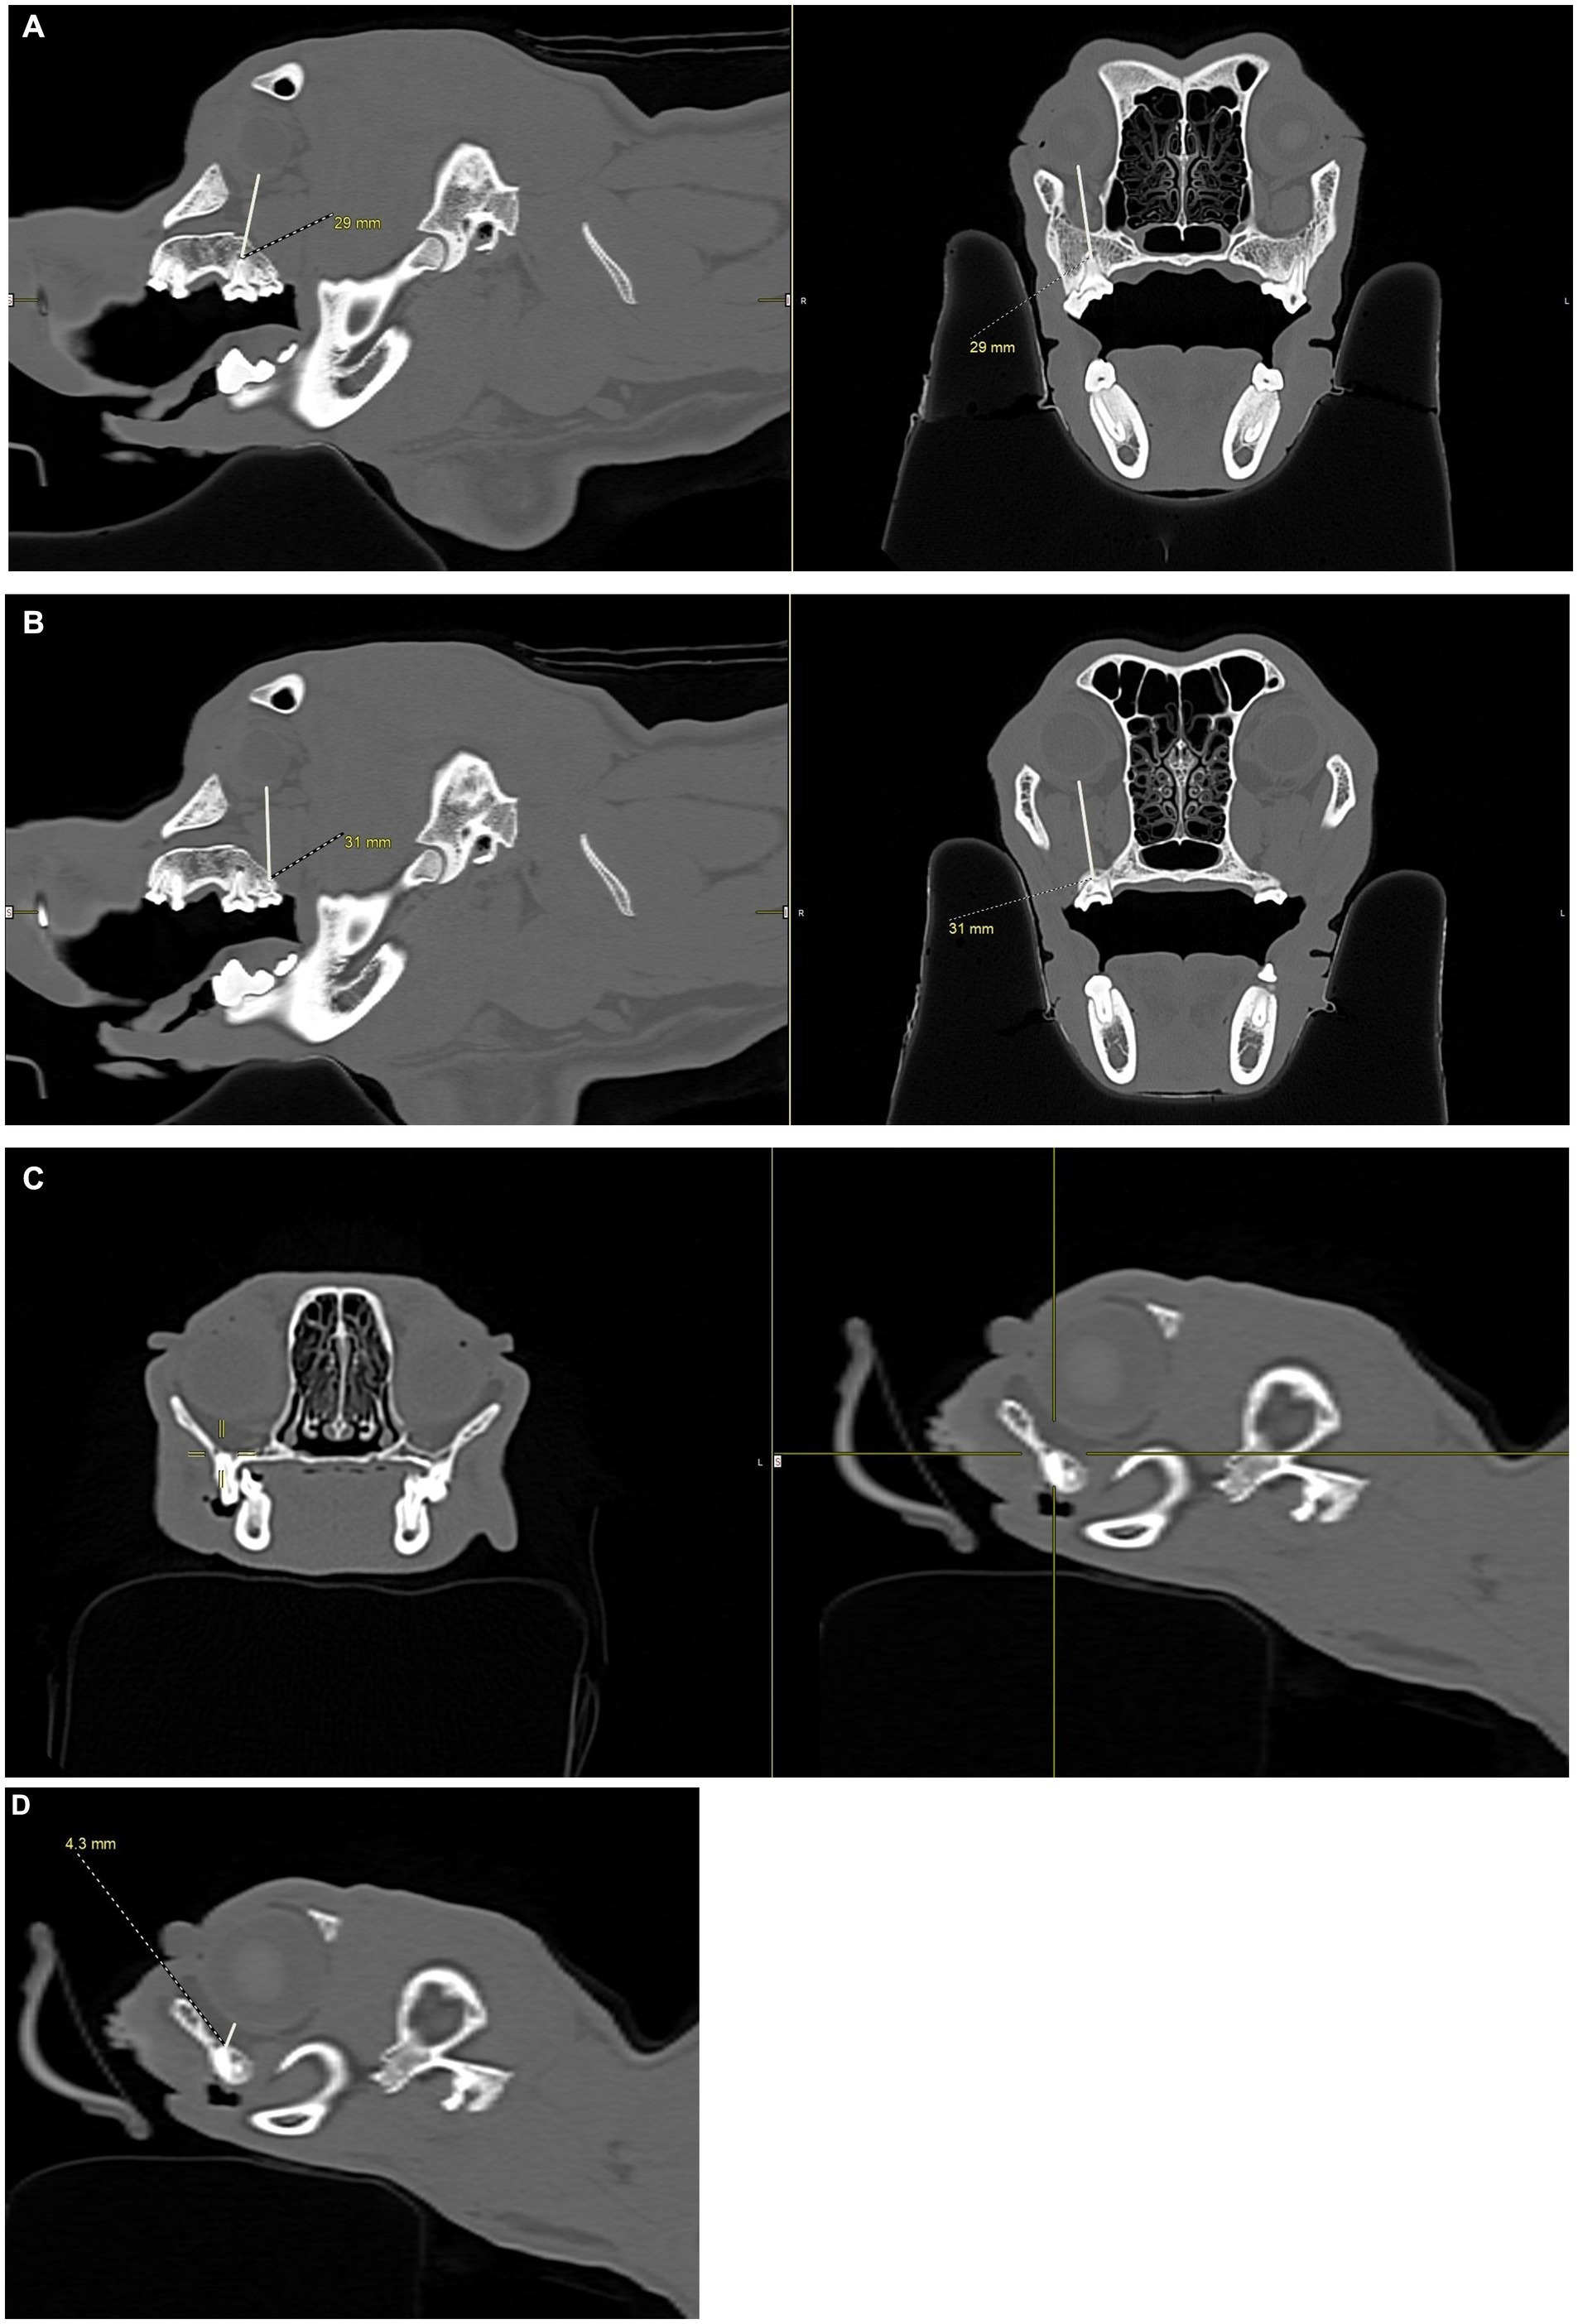

Figure 4

CT scan images showing lateral and transverse views of a dog skull showing measurements between the maxillary first molar root apex and the eye. A measurement of twenty-nine millimeters is highlighted.Alt-text 4B CT images showing lateral and transverse views of a dog skull showing measurements between the maxillary second molar root apex and the eye. A measurement of thirty-one millimeters is highlighted. Alt-text 4C CT scan images showing lateral and transverse views of a cat skull showing the root apex of the maxillary fourth premolar centered in a set of crosshairs. CT image of the lateral view of a cat skull showing measurements between a tooth root apex and the eye. A measurement of four point three millimeters is highlighted.

Figure 4. CT images showing how measurements, in millimeters, were collected from the apices of the maxillary first molar tooth and second molar tooth to the globe in dogs, and from the maxillary fourth premolar tooth to the globe in cats. (A) Distance from the right maxillary first molar tooth palatal root apex to the globe using both the sagittal (left) and transverse (right) views simultaneously for accuracy. (B) Distance from the right maxillary second molar tooth distal buccal root apex to the globe using both the sagittal (left) and transverse (right) views simultaneously for accuracy. (C) Transverse (left) and sagittal (right) views were used to confirm the right maxillary fourth premolar tooth distal root apex. The root apex is visible in the crosshairs on both the transverse and sagittal views. (D) After confirming the right maxillary fourth premolar tooth distal root apex (C), the distance from the root apex to the closest surface of the globe was measured.